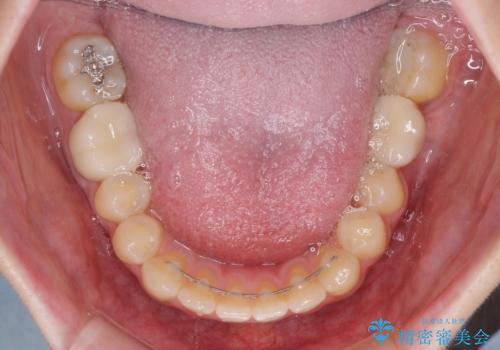

- 口の閉じにくさと割れてしまった奥歯を気にして来院された患者様です。

IPR(歯と歯の間を削る)と歯列全体の後方移動によって口元が引っ込むように設計し、インビザラインにより治療を行うこととしました。

割れてしまった奥歯は抜歯し、矯正治療中の良いタイミングでインプラントを埋入することとしました。

上下正中がずれていたため、抜歯による矯正治療も検討しましたが、口元がそれほど突出していなかったため、非抜歯にて矯正することになりました。

その結果正中のズレは残りましたが、口を閉じたときの感覚や奥歯の咬み合わせには全く問題なく、患者様には大変満足していただきました。